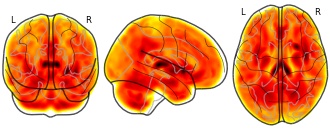

Abstract: Although backward masking is a powerful experimental tool in mitigating visual awareness of facial expressions of emotion, ~20% of participants consistently report being resistant to its effects. In our previous studies, we excluded these participants from analysis as we focused on neural data in individuals who were subjectively unaware of backward-masked facial features that were presented for a brief period of time (e.g., 17 ms). Here, we shifted our focus to potential structural brain difference between aware and unaware participants. To achieve this, structural magnetic resonance imaging (MRI) data were pooled from two recent backward masking studies of emotional faces or eye whites. Out of a total of 64 participants, 12 reported being subjectively aware of the masked faces or their facial features. Whole-brain, voxel-based morphometric (VBM) analysis of structural MRI data yielded significantly greater volume of the posterior thalamus, including the bilateral pulvinar, for the subjectively aware versus unaware individuals. The present findings offer a neuroanatomical basis for visual awareness of emotional content in the form of backward-masked facial features, which complements the known functional role of the pulvinar in such neurobehavioral processes.

Notes: VBM analyses were performed using the VBM8 toolbox for SPM8. Default parameters were used for preprocessing (please refer to the VBM8 online manual: http://dbm.neuro.uni-jena.de/vbm8/vbm8-manual.pdf). For group level analysis, a voxelwise two-sample t-test was used to compare the aware versus unaware groups while controlling for intracranial volume (ICV), study (2010 or 2016), age, and sex. Group level t-map is stored as spmT_0001.nii (ID 55030). Please refer to the images meta data for the experimental variables and covariates. Please use the following link to access the published article associated with this dataset (http://www.sciencedirect.com/science/article/pii/S0028393217304104). For detailed data processing steps, please refer to this article.

Kim MJ, Mattek AM, Burr D & Whalen PJ (in press). Preliminary report on the association between pulvinar volume and the ability to detect backward-masked facial features. Neuropsychologia. doi:10.1016/j.neuropsychologia.2017.10.034